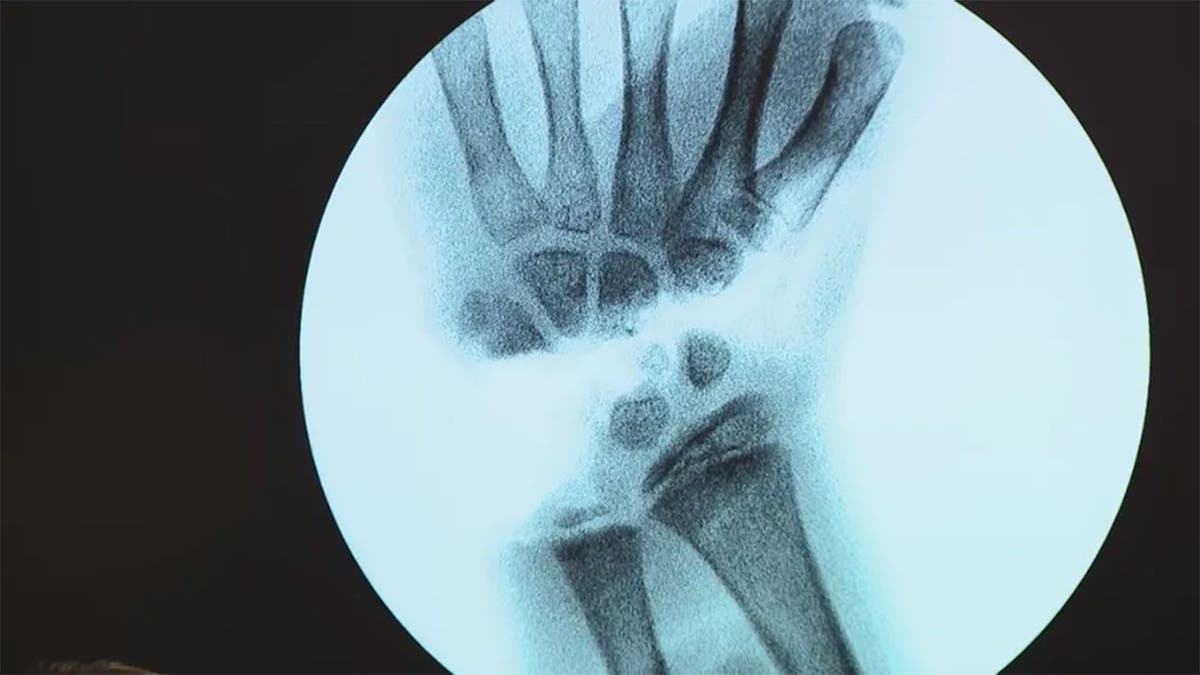

Los cirujanos lograron reimplantarle la mano tras el ataque. Leah, que ahora tiene 10 años, sigue esforzándose día a día por recuperar sus fuerzas.

«Ahora mismo no puedo tocar el piano y no puedo levantar más de 3,6 kilos, pero mi terapeuta y yo estamos trabajando para que recupere la fuerza en la muñeca», le dijo Leah a WZVN.

Los médicos del Tampa General Hospital hicieron todo lo posible por salvarle la mano al niño de 9 años. (WTVT-TV)